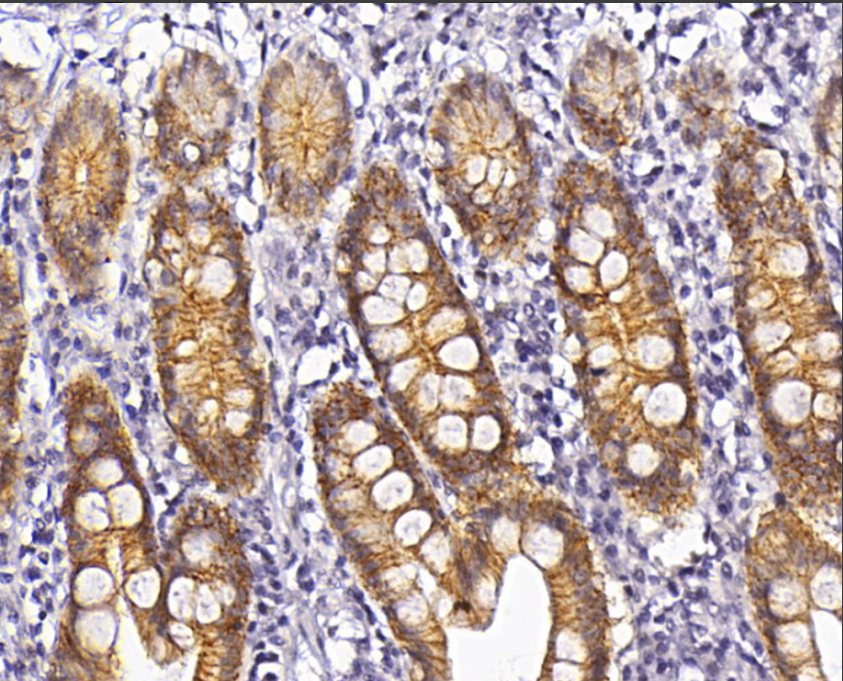

Cellular localization: cytoplasm/membrane

Positive control: Gastric adenocarcinoma/small intestine/rectum

Claudin-3, a protein encoded by the human CLDN3 gene, is a tight junction protein with a molecular weight of 22 kDa and a member of the Claudins family.Claudin-3 is expressed in the junction of ductal epithelium and vesicular epithelium, and up-regulated expression of the gene has been found in ovarian cancers, where its elevated expression leads to an increase in the invasive power and viability of tumor cells. Some studies suggest that Claudin-3 may be a therapeutic target gene for prostate cancer.

Claudin-3 antibody reagents can specifically bind to Claudin-3 molecular antigens. Immunohistochemistry kits containing Claudin-3 antibody reagents are suitable for the auxiliary diagnosis of epithelial tumors (such as ovarian cancer, breast cancer, and prostate cancer).